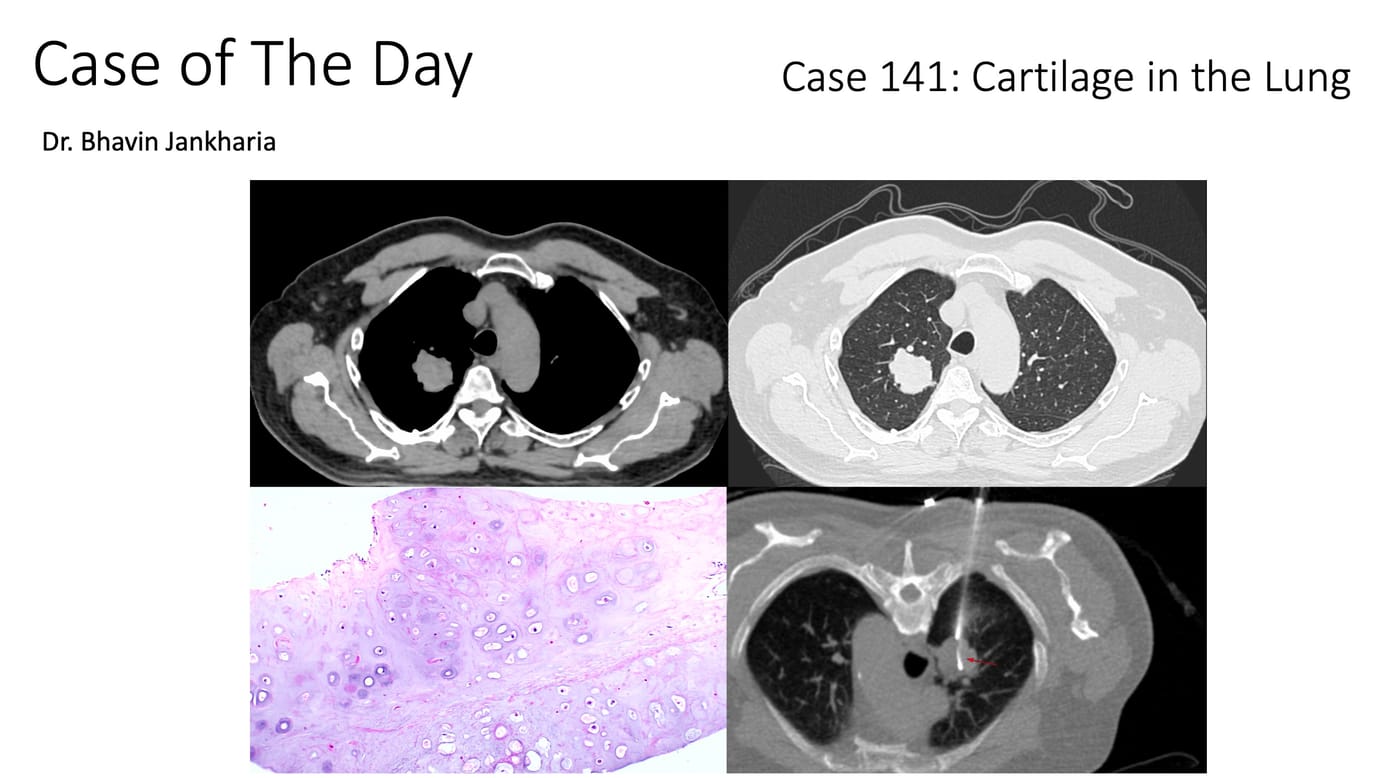

COD 141 - Cartilage in the Lung Members Public

A large mass that bent the needle during biopsy and turned out to be cartilage

Lung Mass